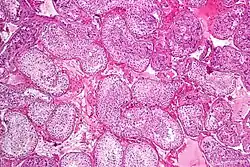

Seminiferous tubule with maturing sperm. H&E stain.

Normal spermatogenesis, testis biopsy.